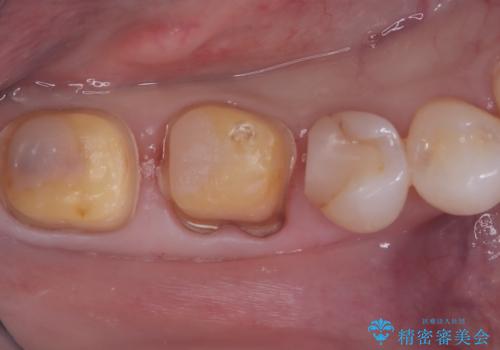

- 右下6番・7番の審美性と機能性を改善するため、セラミッククラウンでの治療を計画しました。1回目の来院時に古い被せ物や虫歯を丁寧に除去し、土台を整えた後に精密な型取りを行います。2回目の来院で仮のセラミッククラウンを装着して噛み合わせや適合性を確認し、最終調整を行います。3回目の来院時に完成したセラミッククラウンを装着し、最終調整を経て治療を完了します。

右下の奥歯にあった古い金属製のクラウンは、見た目の問題や歯ぐきの変色、さらには歯との境目に汚れが溜まりやすいなどの課題がありました。今回は審美的に優れ、生体親和性が高いセラミック素材を使用してクラウンを製作。色調は患者様の天然歯に合わせて調整を行い、自然で違和感のない仕上がりを目指しました。さらに精密な型取りと高度な技工技術を駆使することで、適合精度が非常に高いクラウンを提供しています。治療後は、見た目の美しさと噛み合わせの快適さが向上し、患者様には大変満足いただけました。